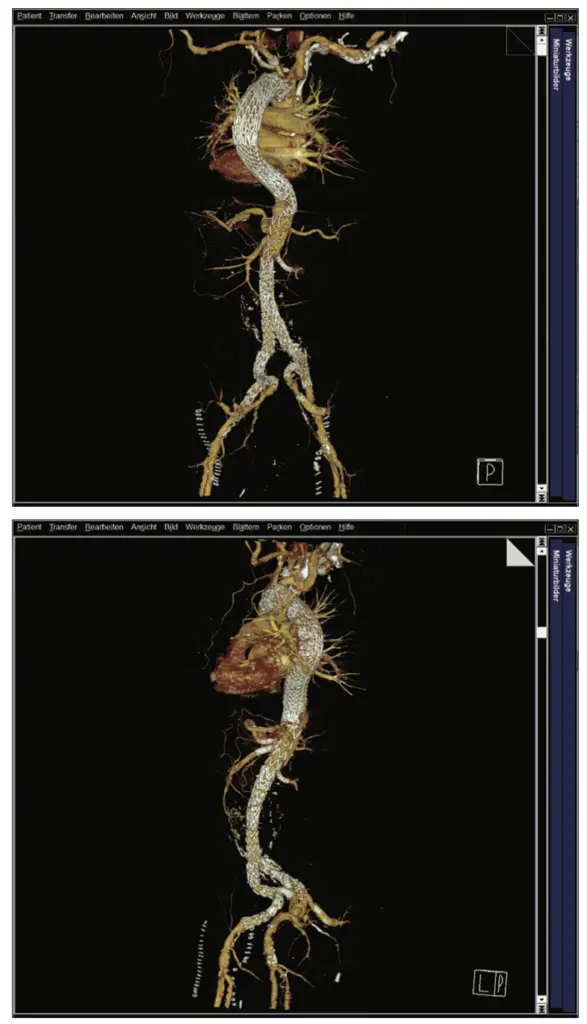

Im Herbst 2023 wurde bei dem damals 62-jährigen Mann als Zufallsbefund im Rahmen einer urologisch veranlassten CT-Untersuchung eine komplexe thorakoabdominelle Aortendissektion Typ Standford B diagnostiziert. Distal setzte sich die Dissektion in ein mutmaßlich vorbestehendes infrarenales Aortenaneurysma fort und bildete ein Aneurysma dissecans von 8 cm Durchmesser. Die Dissektion endete in der linken A. iliaca externa. Zudem bestanden Aneurysmata der A. iliaca externa. Das wahre Lumen war schmächtig im Sinne eines subtotalen True-Lumen-Kollaps.

In interdisziplinären Fallkonferenzen wurden die möglichen Versorgungsoptionen diskutiert und schließlich fiel unter Einbeziehung des Patienten die Entscheidung zu einer dreizeitigen endovaskulären Versorgung. Zunächst erfolgte eine Versorgung der thorakalen Aorta mittels Stentgrafts, die proximale Landezone musste dabei nach vorherigem Debranching mittels Carotido-Carotido-Subclavia-Bypass bis in die Zone 1 nach Ishimaru ausgeweitet werden. Distal erfolgte eine Versorgung der Dissektion der Beckenarterien mit Ausschaltung der Iliacalaneurysmata durch eine beidseitige Implantation eines Iliac-Side-Branch-Devices (Abb. 1 a–c).

Im Dezember 2023 war die abschließende Versorgung mittels individuell angefertigtem thorakoabdominellen Multibranch-Aortenstent mit Landezone in den zuvor implantierten Stents suprarenal bzw. iliacal beidseits geplant. Anatomisch waren zu diesem Zeitpunkt verschiedene Aspekte bekannt und wurden in die OP-Planung, auch zeitlich, miteingeschlossen.

Aufgrund des schmächtigen wahren Lumens sollten Truncus coeliacus, A. mesenterica superior und rechte Nierenarterie mittels Inner-Branches (Custom Design der Firma Jotec/Artivion) erhalten werden. Die linke Nierenarterie wurde explizit nicht miteingeschlossen, da von einem initial funktionslosen Organ ausgegangen wurde.

Als anatomische Normvariante zeigte sich in der Bildgebung ein isolierter Abgang der A. hepatica sin. aus der Aorta entspringend. Geplant war, diesen mit einem Twin-Branch (A. hepatica sin./Truncus coeliacus) zu erhalten. Leider kam es nach der Implantation in den Truncus coeliacus zu einer Kompression und damit zu einem Verschluss der A. hepatica sin. Der entsprechende Anteil des Twin-Branches wurde mittels Vascular-Plug verschlossen.

Trotz dieser positiven Befunde wurde ein langer intensivstationärer Aufenthalt notwendig, da es postoperative Komplikationen wie ein akutes Nierenversagen, eine Pneumonie und ein Delir gab. Allerdings entwickelte sich der Gesamtverlauf schließlich positiv und der Patient konnte über die Reha in die Häuslichkeit entlassen werden. Bildgebend waren die Aneurysmata (abgesehen von einem kleinen Typ 2 Endoleak) ausgeschaltet und die Dissektion regelhaft angelegt. Die Stentgrafts waren einschließlich der viszeralen und iliacalen Branches regelhaft perfundiert (Abb. 5 a und b).